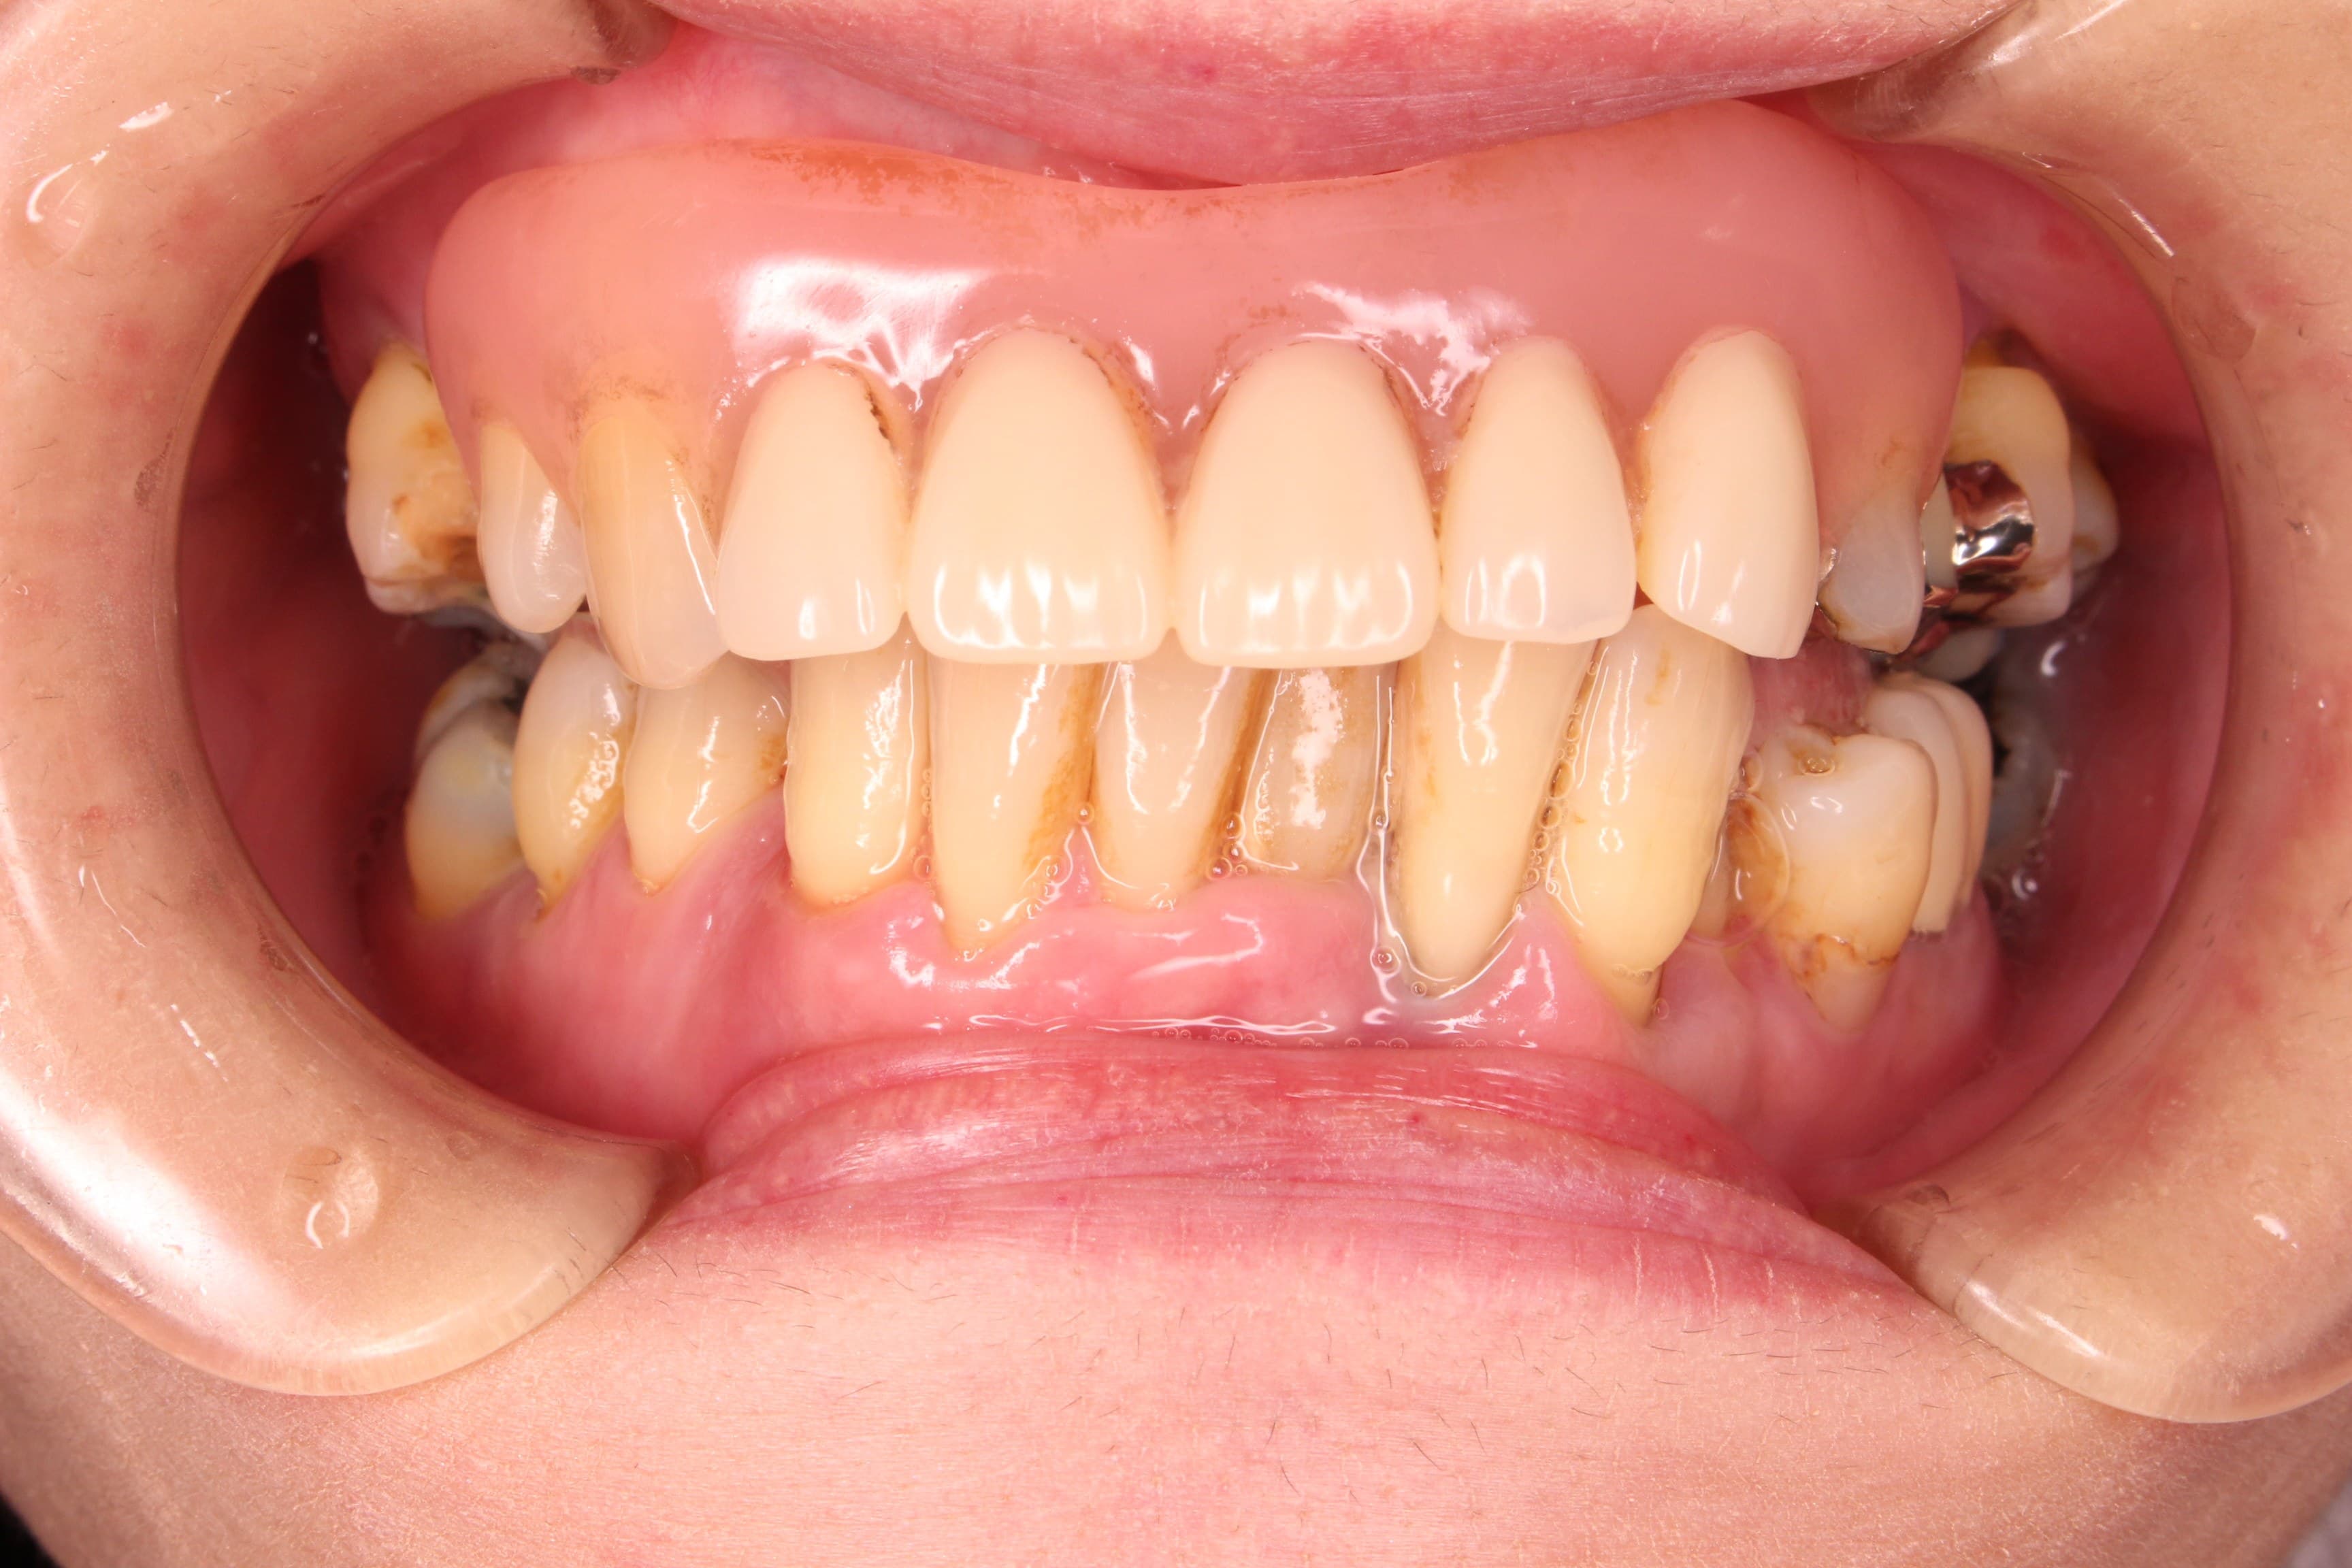

術前

残念ですが、失った骨を20代の頃の様に復活させることはできません。

ただ、歯槽骨(歯を支える骨)が無い歯を残すリスクをご理解いただいた上で、ギリギリまで残しておきたいというご希望に沿うよう、歯周専門治療を行いました。

術後